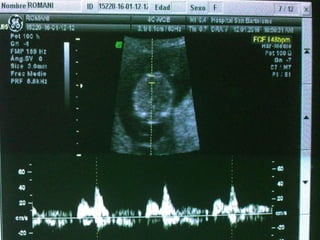

DUCTUS VENOSO

• Vaso pequeño que conecta la vena umbilical con la

proximidad de la aurícula derecha. Tiene un papel crítico

dirigiendo la sangre oxigenada al cerebro fetal

• Un 20% de la sangre oxigenada de la placenta sobrepasa el

hígado y se dirige al corazón fetal. Entra en la aurícula

derecha y luego a la izquierda, a través del foramen oval.

• De la aurícula izquierda pasa al ventrículo izquierdo y luego

a la aorta

VALORACIÓN DV

• Semanas 11+0-13+6 y la LCC entre 45-84 mm. El feto no

debe moverse.

• El tamaño de la imagen debe ser tal que el tórax y abdomen

fetal ocupen toda la pantalla. Se debe obtener un corte

sagital medio del tronco fetal.

• Se debe usar el Doppler color para demostrar la vena

umbilical, el ductus venoso y el corazón fetal. La ventana

del Doppler pulsado debe ser pequeña (0,5-1,0 mm) y debe

situarse en la zona de aliasing normalmente en amarillo